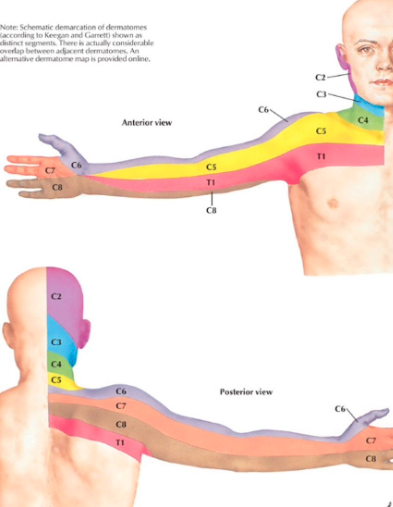

실제 목 디스크나 협착증 등, 신경이 눌렸을 때 어깨부터 팔쪽으로 통증이 뻗쳐나간다.

아래 그림을 보자.

경추 신경이 지배하는 영역을 보여주는 그림이다.

해당 신경이 눌리거나 자극이 된다면, 해당 부위를 따라

통증, 저린감, 감각저하 등이 생길 수 있다.

다시 한번 경추 신경의 지배영역을 보자

빨간색으로 표시한 부분이 아파하시는데

C5-6-7 사이에 해당하는 부분이다.

어깨 자체의 문제가 아니라, 목에 의해 생긴 증상일 확률이 매우 높을 것임을 알 수 있다.